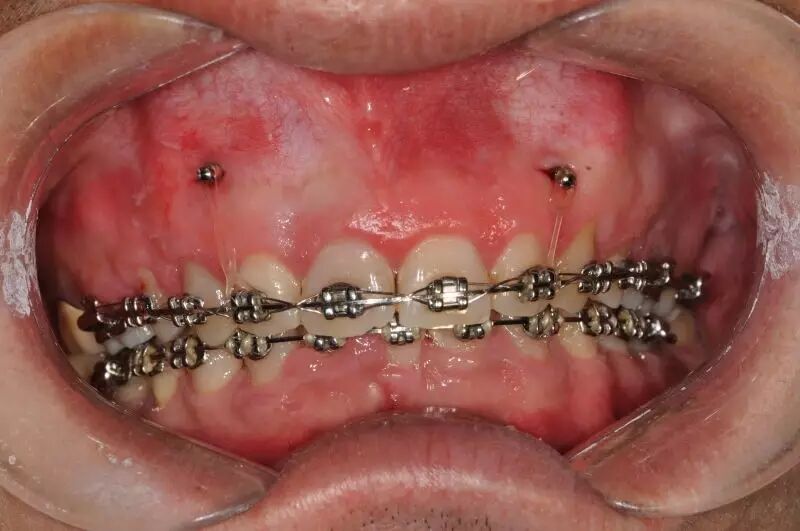

第三种就是依靠在前牙牙槽骨里植入微种植钉,依靠绝对支抗来压低前牙。

其实临床上,牙性深覆合与骨性深覆合往往没有那么大的界限,一个患者可能或多或少同时存在部分骨性因素与牙性因素。所以这些方法也经常混合使用,以达到用最小代价最快打开咬合的目的。

我所要提醒的是,治疗方法是要在诊断正确的基础上才能使用。如果患者骨型是均角甚至是高角,就千万不要使用平导来打开咬合,这样病例的下颌平面角升高、下颌顺时针旋转,患者的面型就会恶化。如果患者有露龈笑,打开咬合就不要再拼命压低下颌牙了,适当压低上前牙会带给患者更和谐的微笑。